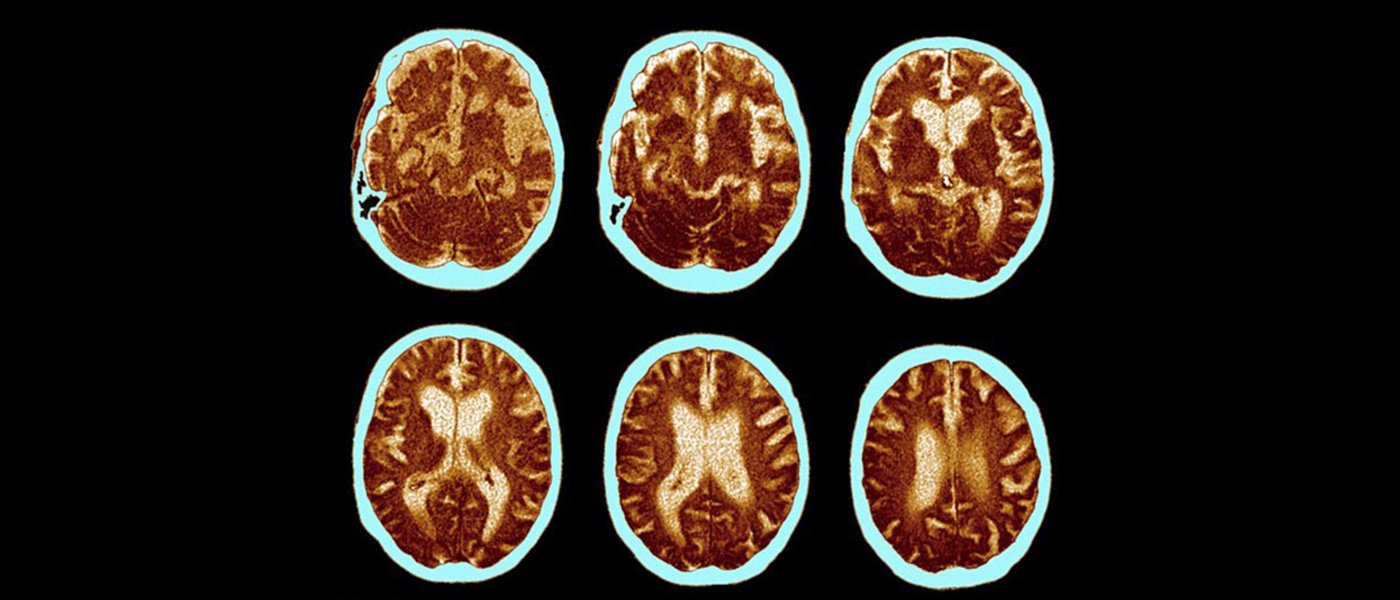

The drug, described in the journal Nature, is called aducanumab, and it targets the toxic amyloid beta plaque, which are tangled clumps of protein that formed in the brains of patients with Alzheimer’s. According to the researchers, the “human monoclonal antibody” prompts the immune system to selectively target and clear the aggregated plaques, which, in turn, could slow down the disease.

Pharmaceutical company Biogen, which funded the trial, said the antibody has been tested in both animal models and a small group of 165 patients with prodomal and mild Alzheimer’s disease. After a year of study, the researchers found that virtually all the amyloid plaques appeared to have gone in patients that were given the highest doses of the drug.

However, the study found that the patients on the highest dose of the drug—10 milligrams for every kilogram of body weight—were also more likely to experience side effects, which can lead to the swelling of the brain.